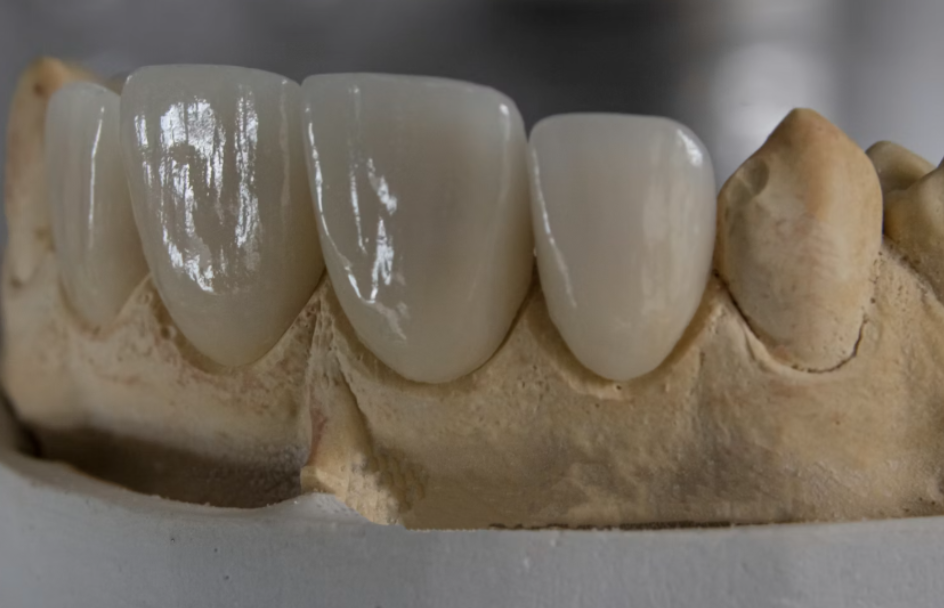

3. Prótesis fija provisional

Mientras nuestro laboratorio fabrica tu prótesis definitiva, te colocamos dientes fijos provisionales. Sales de la clínica con dientes. Hoy mismo.

Sí, al 100%. En la misma intervención colocamos los implantes y una prótesis fija provisional. No te vas con un hueco ni con una prótesis removible. Te vas con dientes fijos, atornillados, funcionales y estéticos. En 3-4 meses la reemplazamos por la definitiva de zirconio o porcelana.